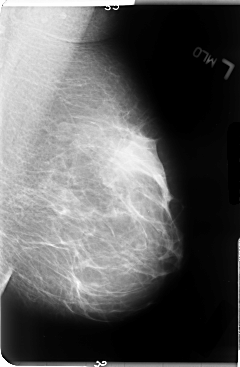

B_3051_1.LEFT_MLO

LEFT_MLO LINES 4760 PIXELS_PER_LINE 3120 BITS_PER_PIXEL 12 RESOLUTION 50 NON_OVERLAY